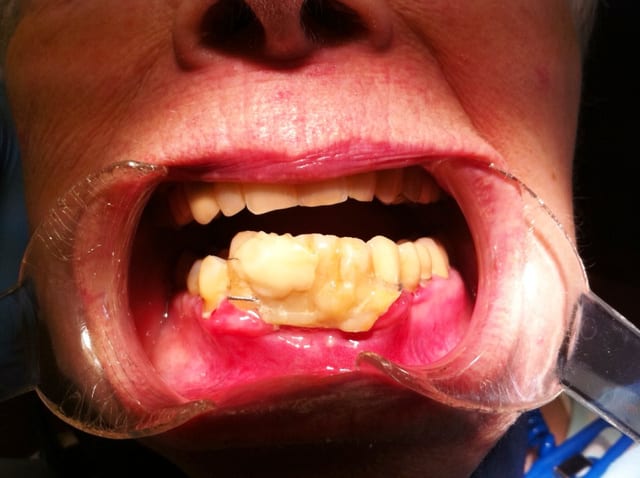

Et pour illustrer mes propos voici quelques photos issus du book of horror que je suis en train de me constituer.

Quand vous tombé là-dessus, quelle est votre réaction? Et surtout quand ça a été commis dans votre propre cabinet pour une somme indécente. Le patient vous demande de finir le travail alors qu'il a déjà dépenser une fortune pour ce résultat. Et il faut prendre en compte le fait que des patients dans cet état j'en ai des dizaines elle que le gars qui a fait ça n'a en aucun cas l'intention de rembourser quoi que ce soit.

Vous voyez, on est loin du niti pété ou de la couronne débordante... Et le monsieur est expert devant les tribunaux...